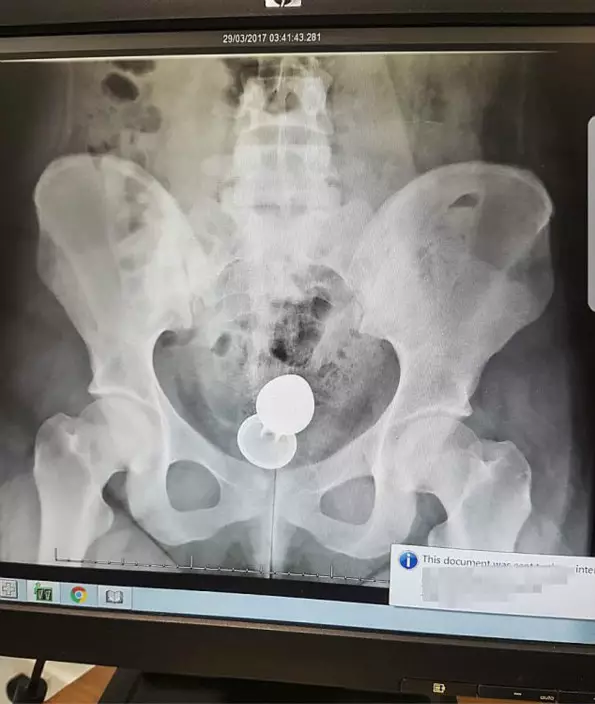

英國西薩塞克斯郡一名20歲少女一夜情時遭男伴把性玩具「肛塞」塞入肛門,但事後肛塞卡在肛門無法取出,男方以有工作在身為由離去。少女事後到醫院接受手術把肛塞取出,醫生指如果她沒及時處理,性玩具可能會刺穿腸道。

20歲的Emily今年三月時與一名男性發生一夜情,期間二人決定以性玩具增添情趣,而男方則拿出4吋長的不銹鋼肛塞,雖然Emily向男伴表示自己從未用過此物,但情到濃時她還是同意使用:「我想他可能太興奮,一下子就放得太入,連手柄部分都放進去了,結果就再也拿不出來了。」驚慌的她馬上向對方表示要去醫院把肛塞取出,但對方竟指隔天排泄時就會自然排出,最後更以隔天要工作為由迅速離去。

醫護人員其後安排她照X光,發現性玩具已進入她的體內深處,由於性玩具是不銹鋼製,其重量令她在等待手術進行時感覺到劇痛。另外,醫生指性玩具上鑲有鋒利的假寶石,有可能會刺穿她的腸道,令她需要依靠俗稱「屎袋」的人造肛門進行排泄,幸好這次她及時求醫才能逃過一劫。